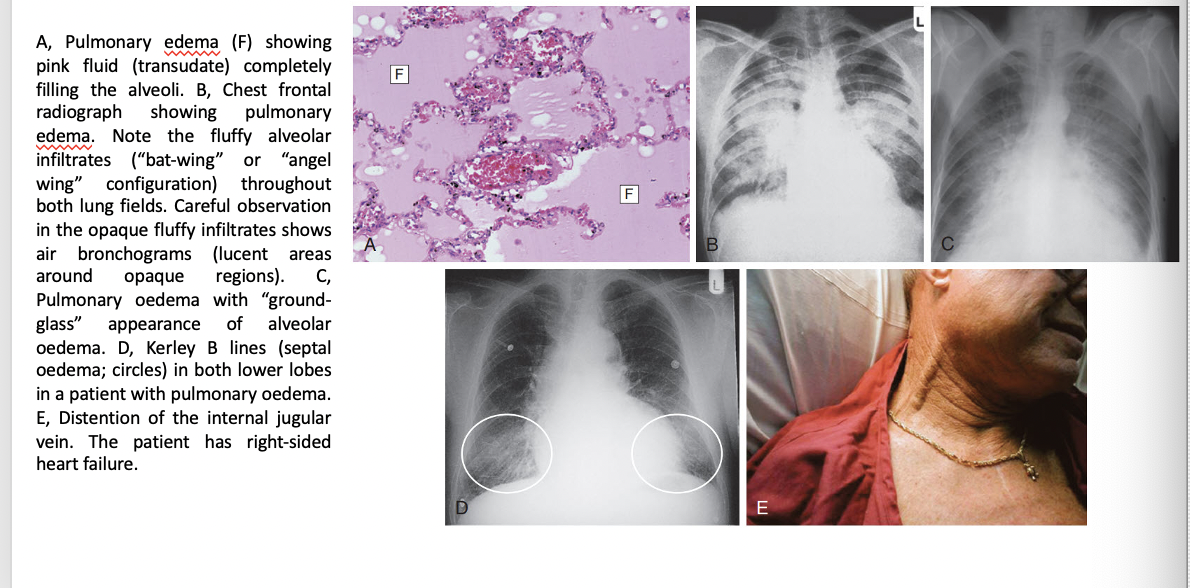

Heart failru efindings/ images